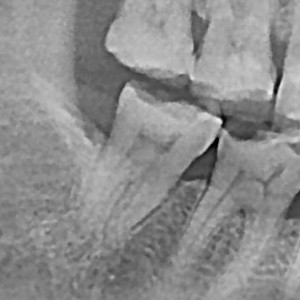

충치치료&신경치료 하루에 끝나는 신경치료